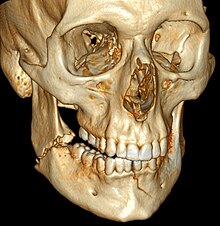

![]() | |

| 3D computed tomographic image of a mandible fracture in two places. One is a displaced right angle fracture and the other is a left parasymphyseal fracture. | |

3D CT reconstruction of mandible fracture, white arrow marks fracture, red arrow marks moderate displacement and open bite